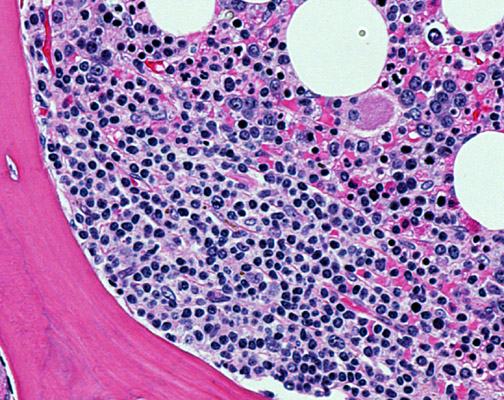

In this high-power view, you can see the cytologic details of the follicular lymphoma cells, including their irregular nuclear outlines and an occasional admixed larger form.